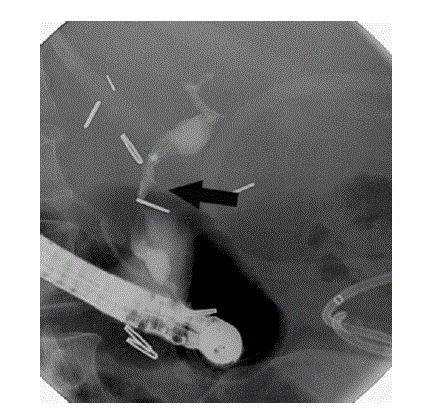

Figure 1. ERCP: stenosis of the common bile duct.